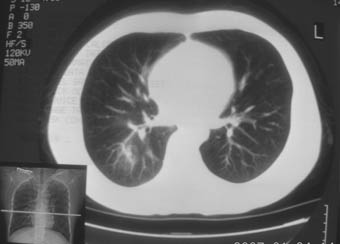

锁骨骨折复查,发现肺内高密度影,行ct检查。

男性,35岁,无任何感觉,无明显发热感冒病史。

右肺下叶背段斑片状阴影,边缘模糊,纵隔内未见肿大淋巴结,病人无发热及感冒史,要考虑浸润型肺结核,可结合ppd检查,或短期抗炎治疗复查。

右肺下叶背段长椭圆型病灶,边缘较规则,无明显分叶征、毛刺,远段未见阻塞征象,病灶较松散,纵隔窗明显小于肺窗,年龄35岁,支气管稍示变窄,纵隔内未见明显肿大淋巴结,这些都不支持肿瘤。病人无任何感觉,无明显发热感冒病史,首先考虑结核(也是结核好发部位),慢性炎症不能完全除外。

右肺中叶不张综合症